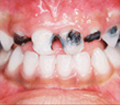

Early childhood Caries is a dental condition that erodes an infant's teeth and occurs when a child's teeth are exposed to sugary liquids frequently or for long periods. Some of these sugary liquids are milk (including breast milk), formula, fruit juice, soda and other sweetened liquids. The problem occurs when this sugary liquid accumulates around the teeth and creates an environment for decay. Some infants will have a high level of decay forming bacteria and will be at increased risk of developing decay if they are given frequent sugary or acidic liquids. Sending your infant to bed with a bottle generates this environment - it is like a mouthful of candy.

A Case of Rampant caries (Nursing bottle caries)